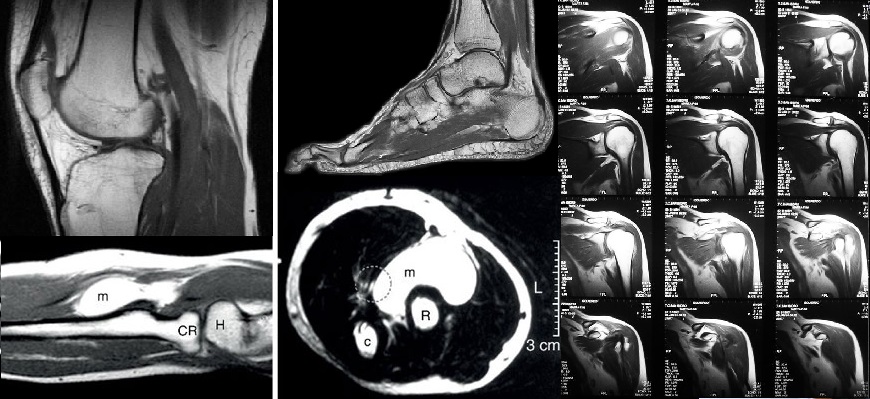

A continuación puedes consultar información general acerca de algunos de los estudios de Resonancia Magnética que tenemos disponibles, solamente da un clic en la imagen deseada: